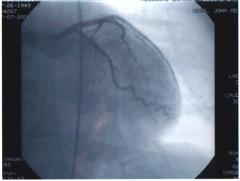

Heart 1 Heart 2